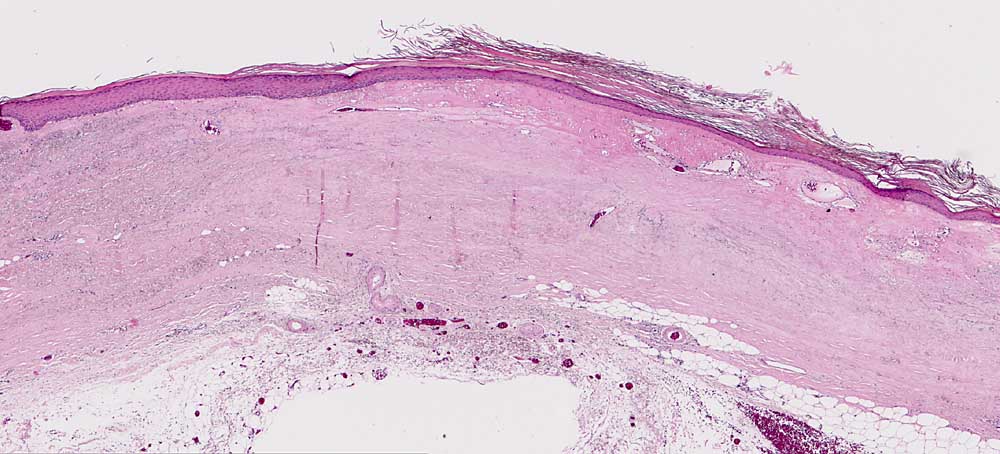

AP/ Chronische Radiodermatitis

Chronische Radiodermatitis

Therapiefolgen

Haut

Haut, Rumpf